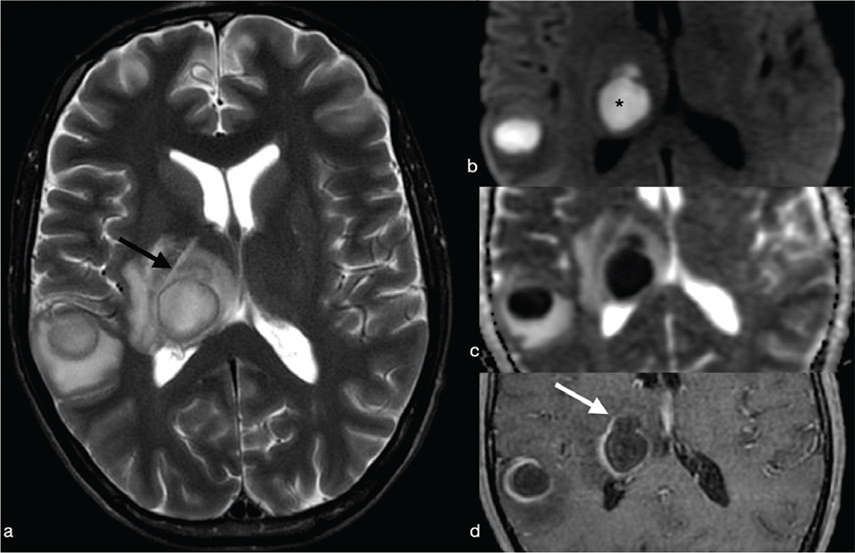

Tuberculous granuloma (tuberculoma) is the most common form of parenchymal CNS tuberculosis. As for pyogenic BA, the cMRI and DWI characteristics depend on the stage of infection: non-caseating, caseating with a solid centre or caseating with a liquid centre (see Table 2). Interestingly, caseating tuberculomas with a liquid centre have an elevated diffusion; indeed, any liquefaction of the central area of necrosis contains a clear fluid, as opposed to pus.7 SWI images may show a complete and regular hypointense peripheral ring.

Tuberculous BA are more similar to pyogenic BA compared to tuberculomas. They usually comprise a multiloculated cavity with central pus, with a thicker wall than a pyogenic BA. It must be distinguished from granuloma with central caseation and liquefaction mimicking pus (Figure 14). However, cMRI does not provide distinction between tubercular and pyogenic BA but lipid peaks without amino acids, on MR spectroscopy, are suggestive of mycobacteria.7

FIG 14. Tuberculoma (a–d) and Tubercular Abscess (e-h). Multiple tuberculomas in both cerebral hemispheres with an hypointense central dot (white arrows in a) within an hyperintense core on T2w are demonstrated. Nodular enhancement on T1+Gd is shown on smaller lesions while the larger one (black arrow in b) shows a thick ring delimitating a cystic core. On DWI and ADC map there is no restricted diffusion (asterisks in c-d). On the contrary, tubercular abscesses located in the quadrigeminal plate show a bright core on T2w, thick peripheral enhancement on T1+Gd (open circle in f) and restricted diffusion on DWI (g) and ADC maps (h).